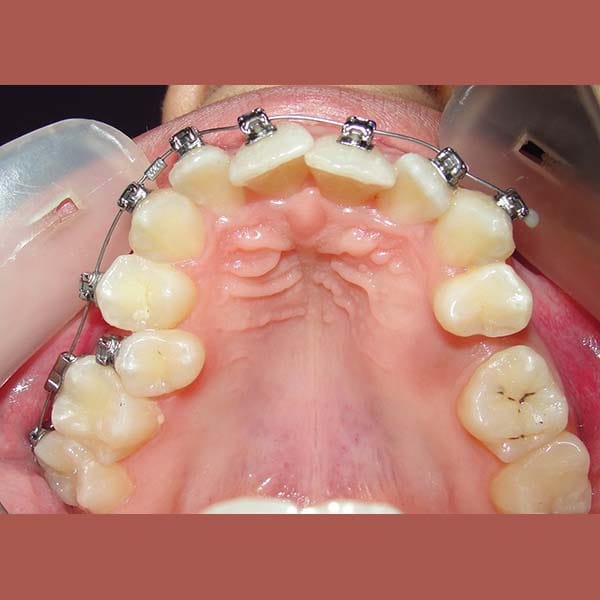

BEFORE

- This young woman suffered from an upper jaw stenosis, crowded teeth, and the absence of one of the upper molars.

She was treated with Daimon braces (an orthodontic device that doesn’t require rubber to fix the archwires, which reduces friction and speeds up treatment).